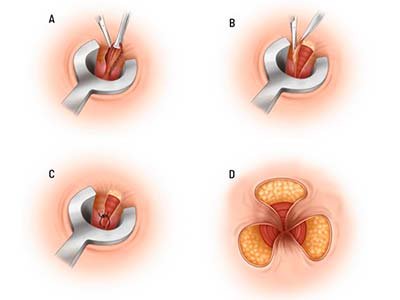

Hemorroidas

Hemorroidectomia tradicional

Ligadura elástica de hemorroidas

Hemorroida a Laser